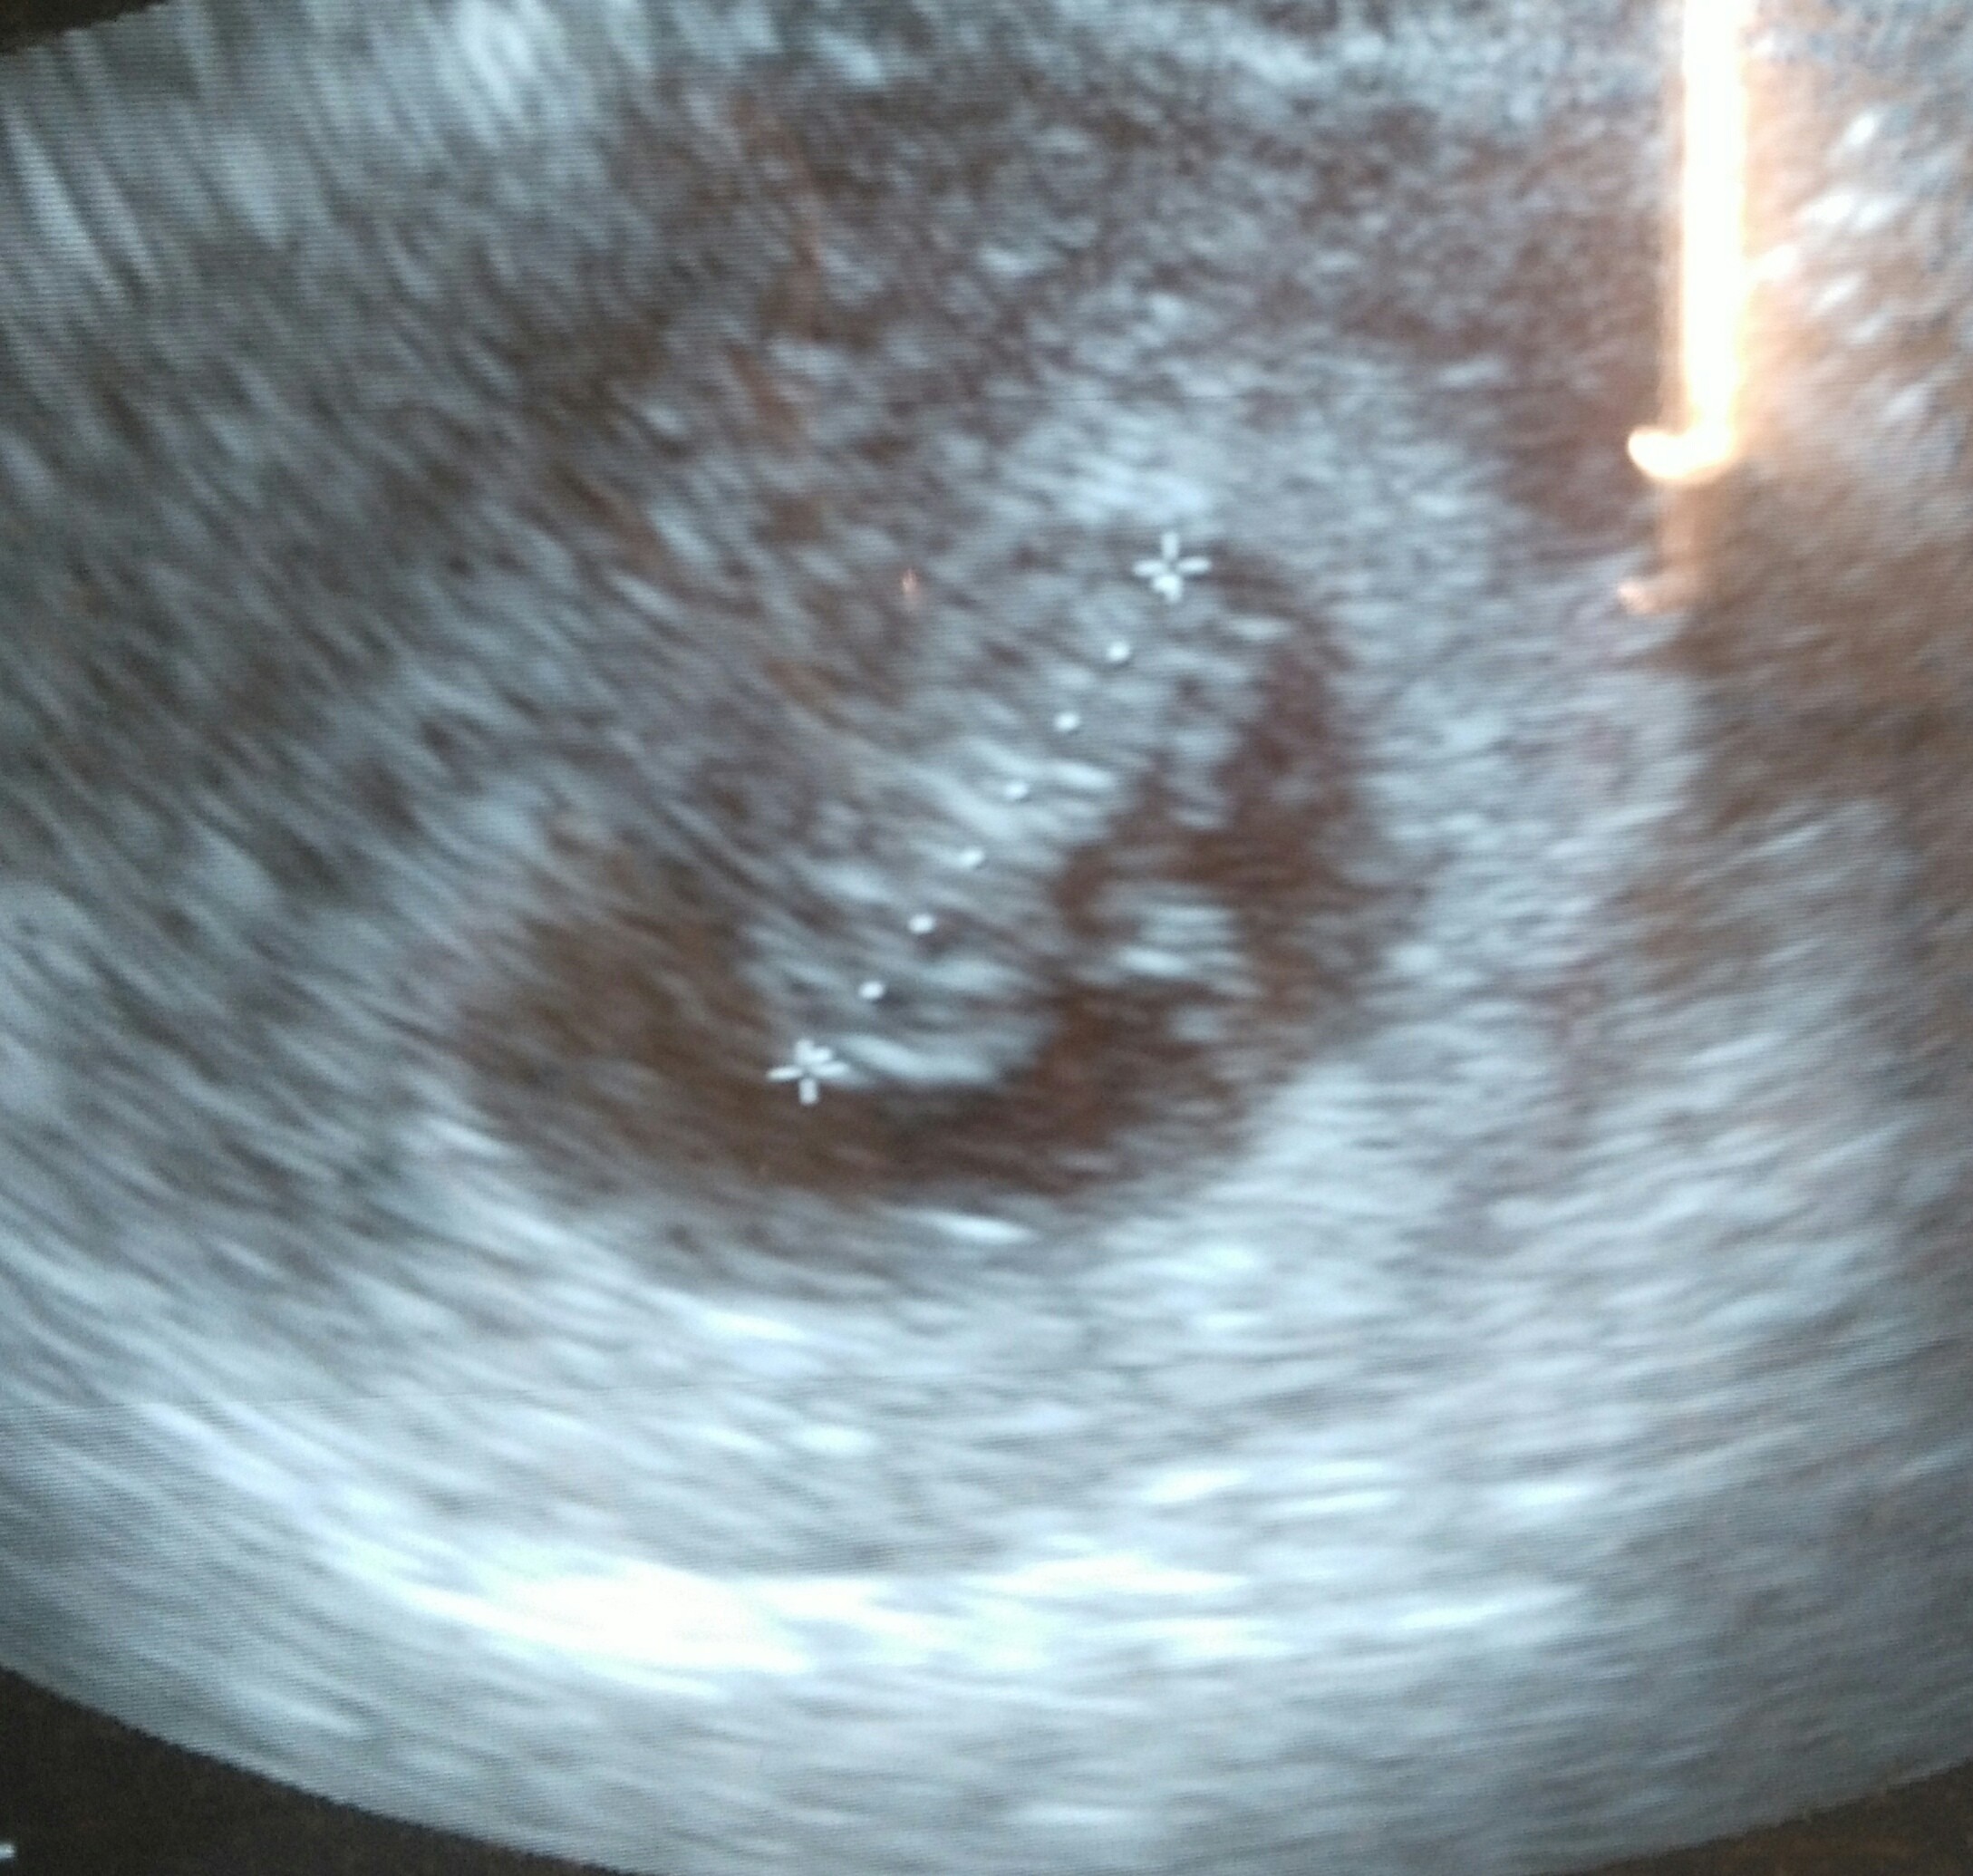

Witam wszystkie stycznioweczki...ostatnio mało sie udzielamnie bo po pracy jestem wykonczona i moje drzemki trwaja wstyd sie przynac co 2-3 godziny.jestem.po wizycie,dzidziol.piekny ma.juz ponad.2cm,wyniki krwi super...ale....pomiar cisnienia wyszedl mi za wysoki wiec juz mam.lekka panike.mam.kontrolowac 2 razy dziennie przez nastepne 2'tygodnie i znow.wizyta....boje.sie.co.z.dzidziolem i czy ewentualna koniecznosc brania lekow.na cisnienie mu nie zaszkodzi czy ktoras z mam cos.moze.doradzic albo miala.podobny problem?oczywiscie odstawiam.ta jedyna.kawe.co ja.pilam.

Przynie okazji pochwale sie maluchem:)

Załączniki

• IMG_20180607_160829.jpg

IMG_20180607_160829.jpg

671,1 KB · Wyświetleń: 97